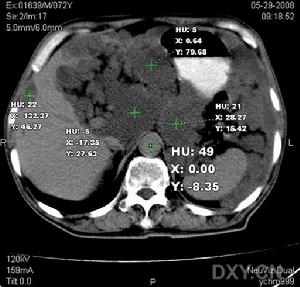

膽汁性腹膜炎影像圖片①膽囊穿孔是發生膽汁性腹膜炎最常見的病因。約10%急性膽囊炎病人將會進展為膽囊穿孔。膽囊穿孔可分為3型,Ⅰ型:游離穿孔,占30%。最常發生於膽囊底,由於局部缺乏保護性粘連而致膽汁流入腹膜腔內,形成膽汁性瀰漫性腹膜炎。Ⅱ型:局限性穿孔,占50%。膽汁溢出至鄰近的臟器(如肝臟、胃、十二指腸、結腸或小腸)、大網膜包裹或粘連,而導致局限性膿腫。Ⅲ型:慢性穿孔,占20%。其多緩慢地進展為膽囊腸瘺。